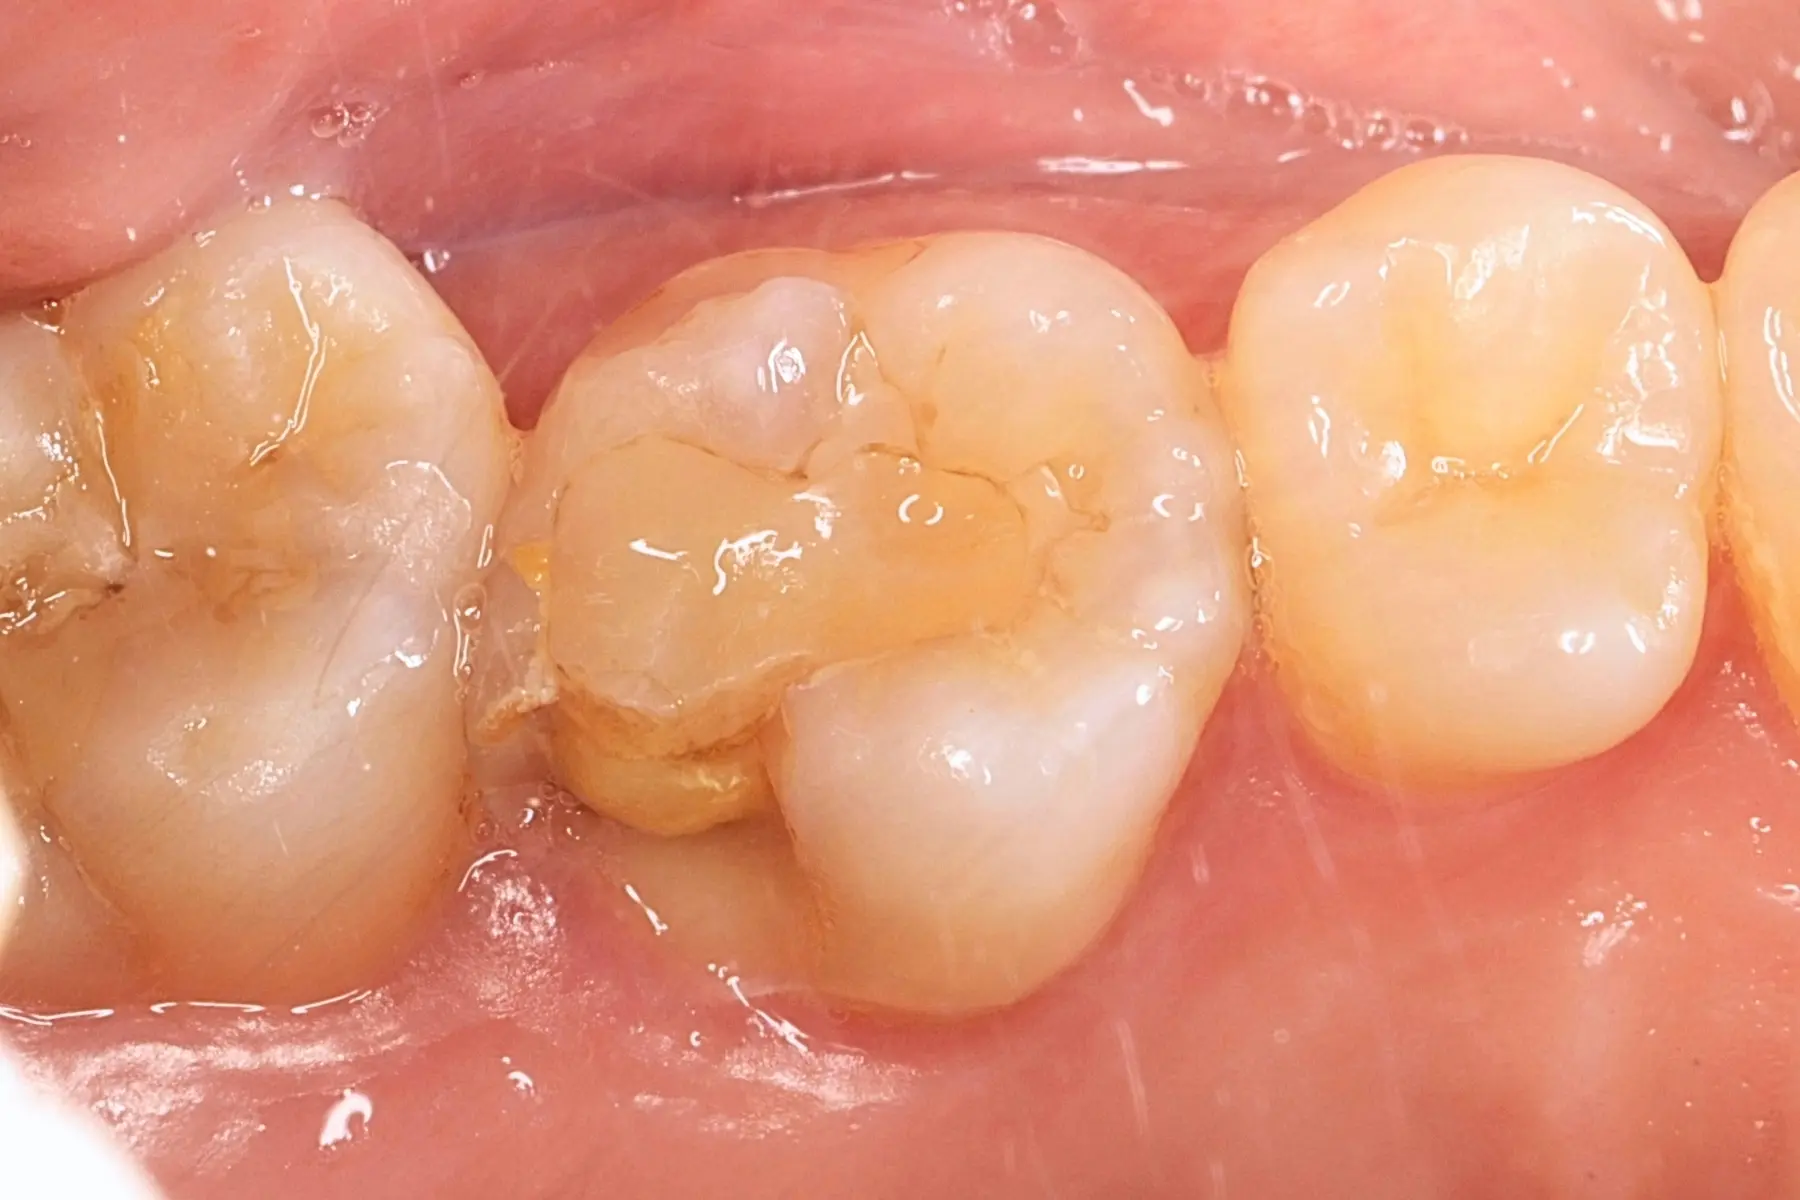

• 術前 43

術後 41

牙橋

主治醫師

• 楊明憲

治療時間

約1年4個月

主訴

吃東西左邊後牙會痛